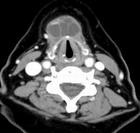

3.多見於小兒和青年。頸前舌骨平面下有圓形腫塊,表面光滑,界限清楚,囊性感,皮膚無粘連,隨吞咽上下移動。沿舌骨方向可觸及索狀物,張口伸舌時可覺腫塊回縮上提。

瘺管或囊腫X線碘油造影有助於明確診斷。但應與鰓裂囊腫、皮樣囊腫及異位甲狀腺相鑑別。